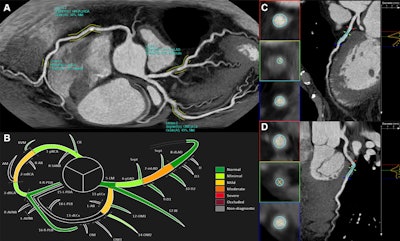

AI reconstruction. (A) Two-dimensional overview of the whole coronary tree obtained from CCTA, as reconstructed by the software. Areas of stenosis are highlighted and visualized together with an esteem of lumen diameter and area reduction, as well as the corresponding CAD-RADS stenosis grade. (B) In another reconstruction, all 18 segments are displayed and colored based on the esteemed CAD-RADS stenosis grade. (C, D) The software provides additional images for each detected lesion, with specific reconstructions to show the reader the exact lumen diameter and stenosis grade. CAD-RADS = Coronary Artery Disease Reporting and Data System, CCTA = coronary CT angiography. Images and caption courtesy of the RSNA.